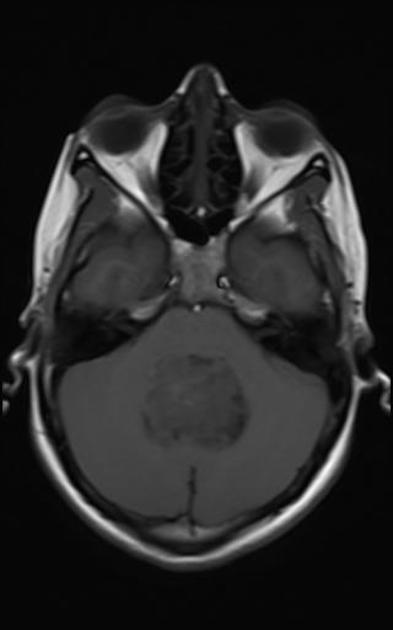

A comprehensive history and physical and MRI imaging of the CNS axis is required. The MRI typically shows a posterior fossa mass which is hypointense to iso-intense on T1 series. It is hyperintense (white) to white matter on T2 series. T1/gad shows heterogeneous enhancement and CT shows calcifications. Once the imaging series is obtained, CSF sampling (particularly in anaplastic Grade III) should be obtained to rule out leptomeningeal seeding. CSI may be required in anaplastic ependymoma.

Ependymoma T1 gad

Ependymoma T1/gad/FS